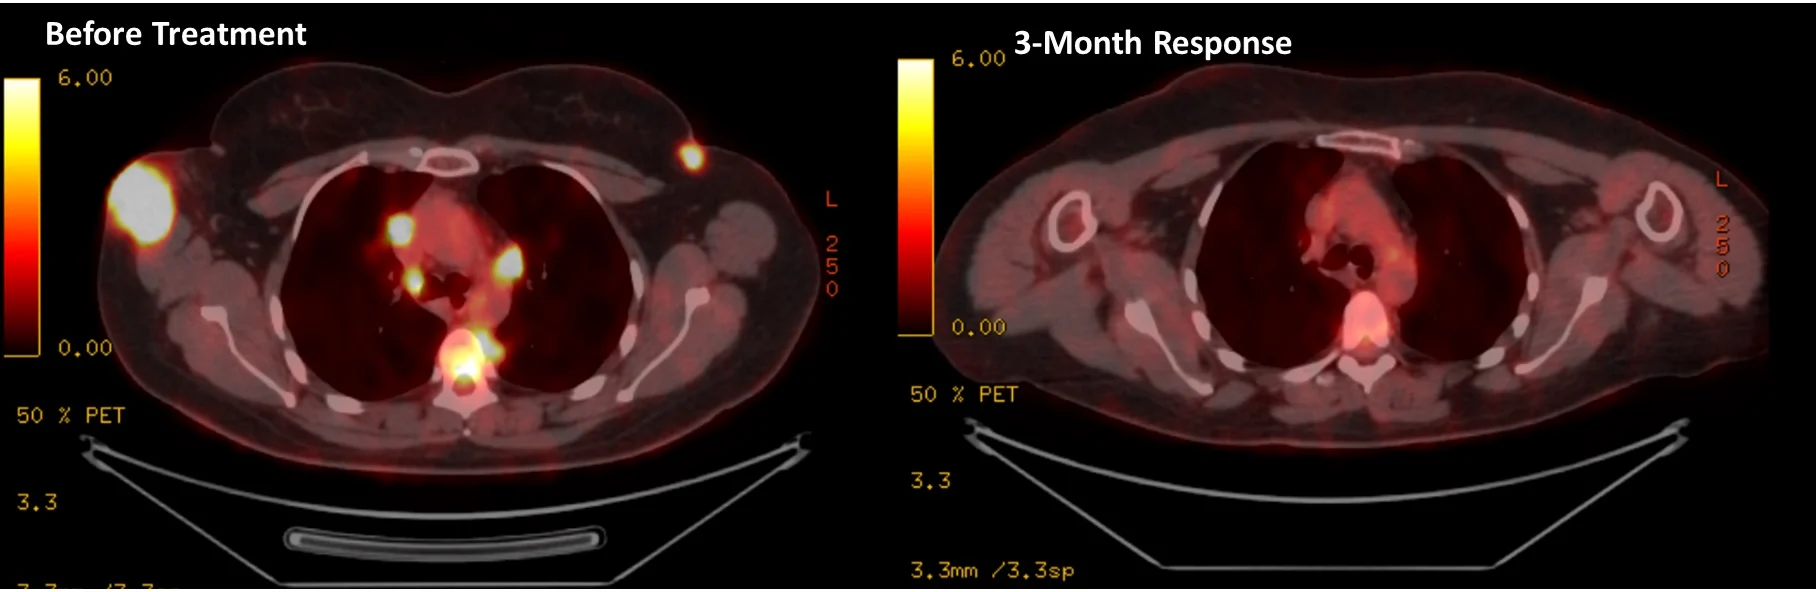

In this patient, we achieved a near-complete response at 3 months (see imaging below).